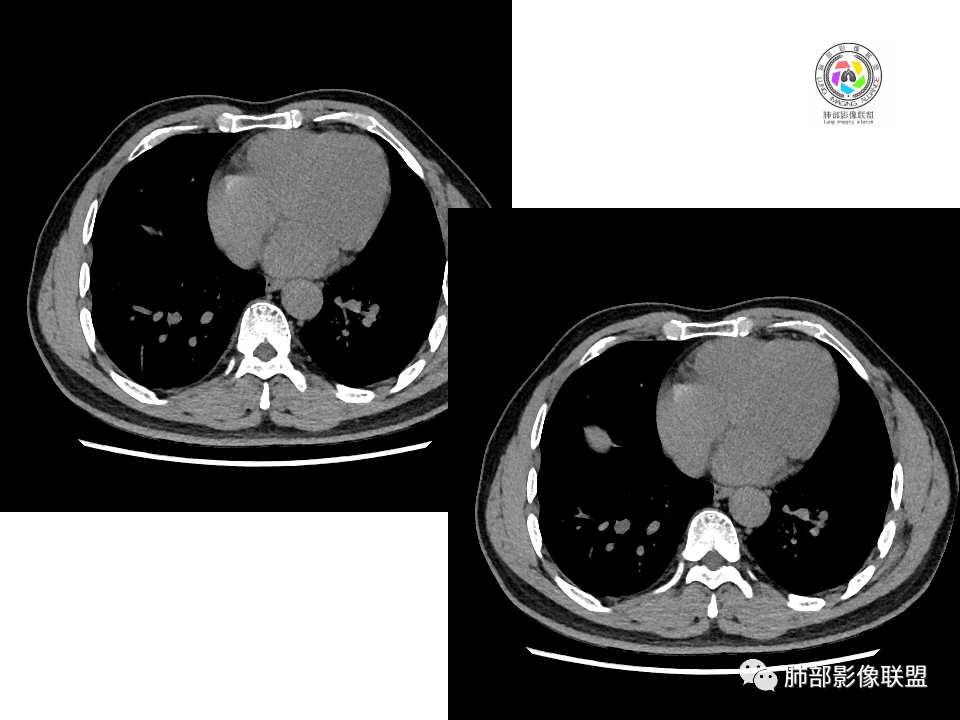

右肺下叶背段胸膜下见团块影,边缘清,其后基底段见一扁平状结节,各见‘’平直及桃尖"征,均轻度强化,右肺上叶背段及中叶外侧段分别少许纤维化灶及部分卫星病灶,一元考虑TB,与隐球菌鉴别!

右肺下叶胸膜下类圆形团块,边缘光滑无毛刺分叶,强化均匀无坏死,另血管旁小结节平直桃尖,上叶小斑片影,考虑结核或者真菌感染。

右肺下叶背段胸膜下见一边缘稍模糊、浅分叶结节灶,密度均匀,似乎轻度均匀强化(具体CT值看不出来),与胸膜锐角相贴,似有平直征和桃尖征。此病灶前内侧还有类似小结节,轻度强化,右肺上叶后段有斑片状稍高密度影:考虑良性病变,炎性结节可能。

晨读,右肺下叶背段胸膜下见肿块影,边缘清晰,未见与气管相连通,右下叶见结节影边缘清晰,两处病变密度均匀,同步不明显强化,中叶外侧段斑点状影,树芽征,考虑1良性病变,结核?隐球菌?2淋巴瘤待除外。

右肺下叶背段胸膜下宽基底团块状占位,浅分叶,边界清晰,胸膜下脂肪间隙清晰,背段支气管管壁似乎增厚,未见明显强化。外侧基底段血管束间结节,边界清晰,亦未见明显强化。中叶外侧段见少许树芽征象。纵隔未见明显肿大淋巴结。我先猜个结核。

男性,49岁,体检发现,右肺下叶背段胸膜下见肿块,边界清楚,边缘光滑,胸膜下脂肪间隙存在,有分叶,无毛刺,均匀强化,内无坏死,右肺下叶血管束间不规则实性结节,边界清楚,无明显强化,中叶少许斑片状高密度影,纵隔未见明显增大淋巴结,考虑良性病变。

右下肺占位并淋巴结肿大,边缘光滑,强化不明显,指状突起。考虑恶性肿瘤,不除外小细胞,鉴别诊断肺结核。

中年男性,体检发现病灶,右肺下叶背段胸膜下见团块影,边缘清晰,与气管关系不密切,右肺下叶见一小结节影,边缘清晰,两处病变密度均匀,增强病灶强化不明显,偏向良性病变,隐球菌?炎性假瘤?

右肺下叶肿块,边界清楚,边缘有晕,光滑,无毛刺,均匀强化,无坏死,中叶少许斑片状高密度影,粘液栓,考虑良性病变,隐球,鉴别结核。

中年男性,有吸烟史,右肺下叶靠近胸膜下类圆形肿块,边缘光滑,有膨隆,浅分叶,周围有磨玻璃影,附近有血管进入,与支气管关系不大,宽基底与胸膜相连,胸膜增厚不明显,密度均匀,轻度强化;右肺下叶近端有一不规则结节,有血管贴边征,右肺中叶外侧段斑片影。右肺下叶靠近胸膜下肿块考虑恶性神经内分泌肿瘤,大细胞肺癌可能性大。靠近肺门端结节考虑转移?右肺中叶炎症。鉴别隐球菌肺炎。

中年男性,无症状,右肺下叶背段团块影,边缘清晰,周围晕征,增强病灶强化不明显,考虑隐球菌。

右肺下叶二个大小结节,胸膜下结节浅分叶,指状突起,轻度强化,较小结节血管漂浮,考虑小细胞癌,类癌,鉴别隐球菌。

右肺多发结节,较大位于胸膜下,宽基底与胸膜相连,边缘光滑,分叶不明显,局部周围似有模糊GGO,支气管显示不佳,平扫密度均匀,增强后强化不明显,考虑良性,IMT,隐球菌,鉴别小细胞癌。

右肺下叶胸膜下肿块影,边界清晰,无明显分叶及毛刺,无晕征,未见明显卫星病灶,内无钙化,增强后均匀强化,未见明显坏死,近肺门侧小肿块,与血管无关,需要连续层面看与支气管的关系,无关就是淋巴道,考虑小细胞癌有可能,近肺门是淋巴转移途径?

体检发现右肺下叶胸膜下类圆形肿块,边界清晰,有膨胀感,胸膜下脂肪间隙清晰,密度均匀,增强轻度均匀强化。另右肺下叶血管束间可见一小结节影,与胸膜下大结节类似。考虑为良性病变。

中年男性,体检发现,有吸烟史。影像见右肺多个结节、肿块影,大者位于背段,靠近胸膜下类圆形肿块,密度较均匀,边缘光滑,有膨隆,浅分叶,周围有磨玻璃影,有血管进入,似与支气管关系不大,宽基底与胸膜相连、扶墙,轻度强化;纵隔内无明显肿大淋巴结。首先考虑炎性隐球菌可能,需鉴别:肿瘤病变转移。

中年男性,28年吸烟史,肺内多个病灶,较大病灶位于胸膜下,边缘较光整,宽基底,胸膜局限性增厚,支气管壁无明显增厚,与周围支气管关系不是很密切,不明显强化,常规考虑炎性病变,恶性小细胞癌属于崽大?

中年男性,20余年吸烟史,体检发现,右肺下叶胸膜下软组织肿块,边界清楚,边缘平直,有压迹,密度均匀,增强强化不明显,未见坏死区,考虑良性可能,炎性肉芽肿?。右肺下叶一小结节影,多个层面均有,考虑整体呈管状,走行与支气管相似,增强强化不明显,支气管来源可能,粘液栓?右肺中叶外周见斑点状、小结节状影,炎性病变?一元论,支气管来源病变,支气管囊肿?粘液栓?阻塞性炎症?长期吸烟史,鳞癌不除外。

右肺下叶胸膜下结节,膨隆为主,胸膜糊墙,类山丘正,邻近血管增粗,其内侧肺门方向另见一小结节,均轻度强化,强化程度类似,长期吸烟史,首先考虑小细胞癌,鉴别炎性结节。

中年男性,体检发现占位。右肺下叶背段胸膜下肿块,周围晕征,有小分叶,与支气管、肺内血管关系不清,形似山丘,重建可见肿块呈D字形凸向肺部。似跨斜裂,似有小凸起与肋下缘相连,增强似有轻微均匀强化。右肺下叶外基底段小结节,位于血管周围,部分边缘平直,轻微均匀强化。考虑二元:一、右下叶背段肿块为肺外病变,神经鞘瘤?SFT?鉴别小细胞癌、隐球菌病;二、右下叶外基底段结节考虑为良性结节、炎性肉芽肿?

大小两个结节,形态类似,强化一致,都是乏血供病变,也无明显坏死,不符合炎性肉芽肿强化特点了,大结节膨隆明显,有局部突出,有长期吸烟史,所以考虑神经内分泌肿瘤可能(小细胞>不典型类癌),另外不典型错构瘤需要鉴别。最终还是需要穿刺病理确定。

2.右肺下叶背段胸膜下块影,边界清楚光整,上下极见磨玻璃晕,未见明显分叶毛刺和棘状突起,未见胸膜凹陷或胸壁侵入。密度均匀,轻度不均匀强化。未见支气管进入。

3.右肺中叶外侧段胸膜下散在小片影,磨玻璃密度为主,边界不清,支气管相关。符合炎性特征!

4.右肺下叶基底段支气管血管束旁小结节影,边界清楚,强化不明显。注意,这结节在“遥远的”基底段。